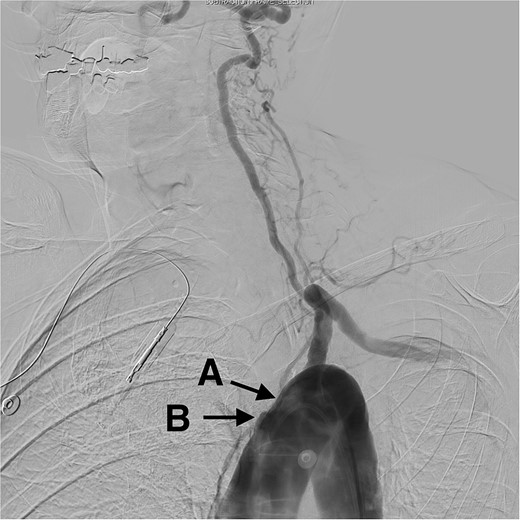

A cerebral angiogram demonstrated left common carotid occlusion (Fig. 1A) and the occlusion of the origin of the right brachycephalic trunk (Fig. 1B). Consequently, the left vertebral artery is the only cerebral vessel from the aortic arch filling anterogradely, resulting in retrograde flow to the brachycephalic trunk and of the right common carotid artery and right vertebral artery (Fig. 2A–D). The left internal carotid artery is filled from the left occipital artery, which is filled by the left vertebral artery. Intracranially the patient has the posterior communicating artery and the anterior communicating artery.

Digital subtraction angiogram demonstrating: (A) occlusion in the origin of the left common carotid artery. (B) Occlusion at the origin of the brachycephalic trunk artery.